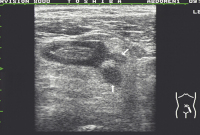

Kolon-Divertikulitis: Diagnostik und sonographisch gesteuerte Therapie

Journal für Gastroenterologische und Hepatologische Erkrankungen 2009; 7 (2): 13-18 Volltext (PDF) Summary Praxisrelevanz Fragen zum Artikel Abbildungen